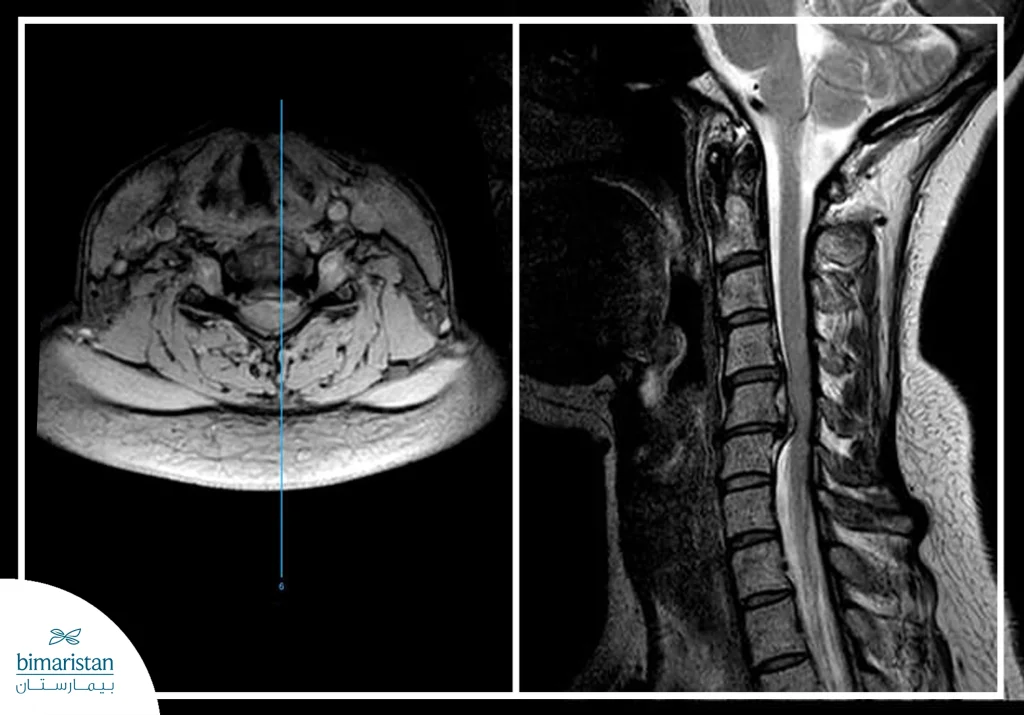

- التصوير بالرنين المغناطيسي MRI: يُعد التصوير بالرنين المغناطيسي أكثر أنواع التصوير حساسيةً لفحص الأقراص الغضروفية بين الفقرات، إذ يتميز بقدرته على إظهار الأقراص والأنسجة الرخوة المجاورة والأعصاب المحيطة بطريقة أوضح بكثير من طرق التصوير الأخرى.